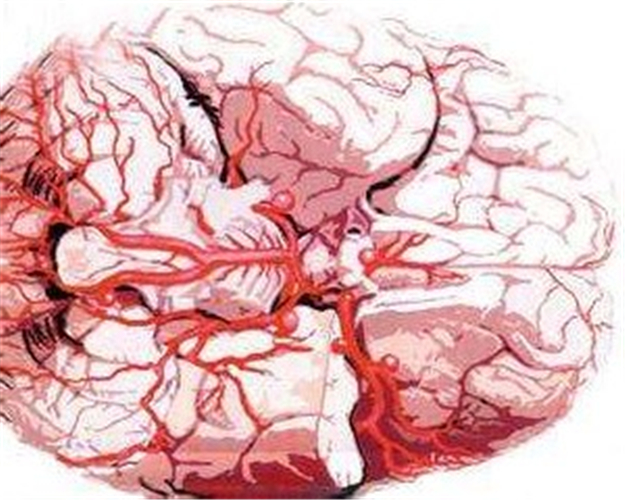

腦血管痙攣圖片

腦血管痙攣的病理圖

腦血管痙攣的位置漫畫

腦血管痙攣漫畫

腦血管痙攣

腦血管痙攣危害